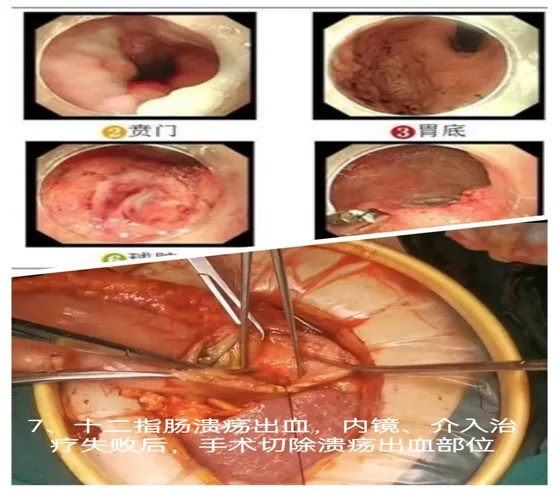

07内镜、介入保守治疗无效的十二指肠溃疡出血:手术治疗的紧急干预

72岁男性患者,因糖尿病并发症入院,合并高血压和肾功能衰竭。入院后,患者出现多次排黑便,且量较大,血红蛋白一度下降至51g/L。尽管输血后血红蛋白有所回升,但效果不明显,且患者的贫血未能得到有效改善。内镜检查发现十二指肠球后直径1.2cm的溃疡并有持续出血。尽管进行了内镜下止血治疗,并给予药物促进溃疡愈合,效果依然不佳,患者的血红蛋白继续下降。随后,进行急诊介入治疗,实施胃十二指肠动脉栓塞术,但5天后,患者再次出现出血性休克。在我科会诊后,急诊进行“十二指肠溃疡并远端胃切除+R-Y吻合术”。术后,患者血红蛋白逐渐稳定,生命体征逐步好转,最终顺利恢复。

难点总结:本病例的难点在于十二指肠溃疡反复出血且内镜及介入治疗均未能有效控制病情。患者合并糖尿病、肾功能衰竭等多种基础疾病,进一步加大了手术风险。在此情况下,及时进行外科手术干预至关重要。

推荐理由:通过及时的手术治疗,术中胃腔明确出血部分后行溃疡切除,成功止血,体现了外科手术在紧急情况下的关键作用。